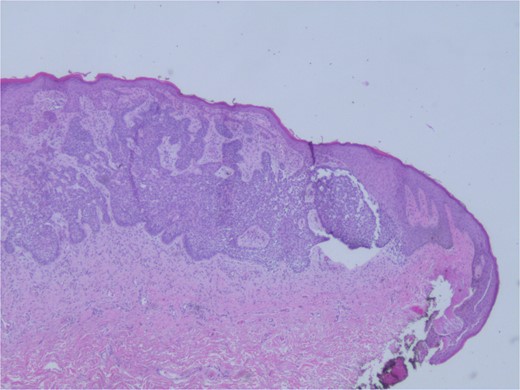

At the time of the surgery, the lesion was excised with 5 mm margins, given the acceptable margins of 4 mm for nonmelanoma skin cancer [4]. Macroscopic examination of the lesion revealed a well-defined, hyperpigmented, macular lesion with pathology positive for infiltrating BSC with negative margins confirmed on histology. Histology was notable for predominantly basal cell morphology with areas of squamous differentiation. The presence of the basal cell carcinoma component is demonstrated (Fig. 1). The BSC with abnormal squamous keratinization is also demonstrated (Figs 2–4). These studies were conducted on routine hematoxylin and eosin stains confirming the diagnosis of BSC. The patient was seen in the office, and at 2 months postoperative, there were no clinical concerns.

Microphotograph revealing BSC with abnormal squamous keratinization on histology.